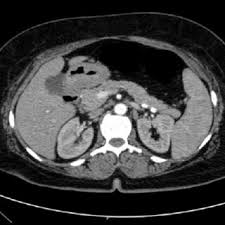

Micro-CT cross-sectional image showing internal porosity and micro-architecture

Micro-Computed Tomography (Micro-CT) is a high-resolution, non-destructive 3D imaging technique that uses X-rays to visualize and quantify the internal structure, porosity, density distribution, and micro-architecture of materials and biological systems. By reconstructing the full sample volume into three-dimensional datasets, Micro-CT enables detailed examination of internal features without sectioning or damaging the specimen.

At Materials Metric, Micro-CT is used to analyze internal defects, cracks, voids, interfaces, and spatial organization in biomaterials, tissue scaffolds, additively manufactured components, composites, foams, devices, and engineered materials. This capability is essential for research and development, failure analysis, preclinical studies, additive manufacturing evaluation, and quality control where internal structure directly governs performance and reliability.